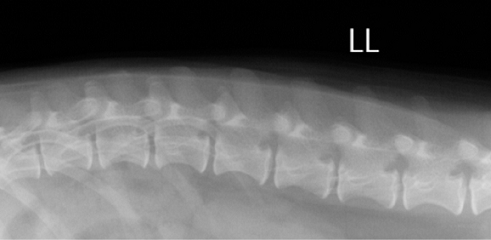

【画像診断】~ダックスフンド、雄10歳、グレート3の椎間板ヘルニア~

▲ダックスフンド、病変部は胸椎T13-腰椎L1の単純X線検査像の側面像